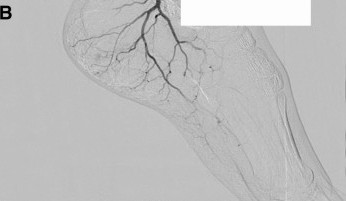

Plantar Fasciitis Embolization (PFE)

PFE (also described as transarterial embolization/microembolization for plantar fasciitis) is an image-guided outpatient procedure intended to reduce abnormal “pain blood vessels” (neovessels) associated with chronic plantar fascia irritation.

Before

After